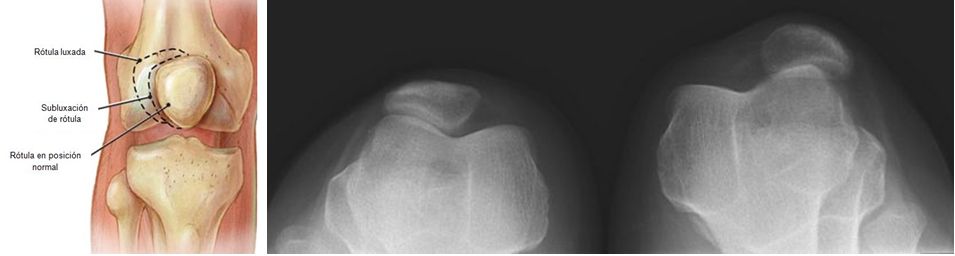

SEMIOLOGIA DE LOS MIEMBROS INFERIORES